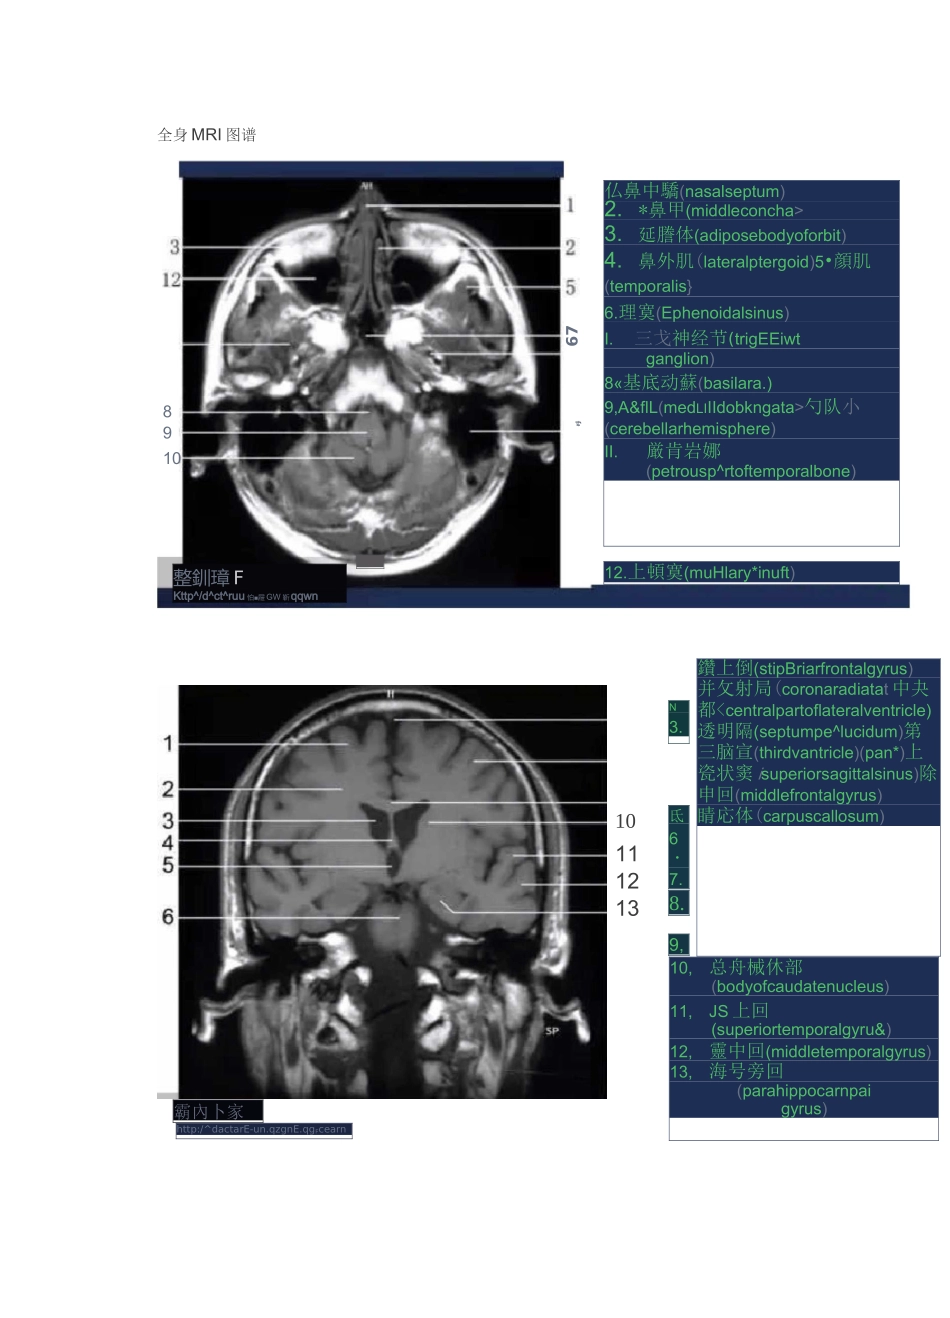

全身 MRI 图谱12.上頓寞(muHlary*inuft)整釧璋 FKttp^/d^ct^ruu 怕■屜 GW 靳qqwn8910rJ67仏鼻中驕(nasalseptum)2.*鼻甲(middleconcha>3.延謄体(adiposebodyoforbit)4.鼻外肌(lateralptergoid)5•顔肌(temporalis}6.理寞(Ephenoidalsinus)I.三戈神经节(trigEEiwtganglion)8«基底动蘇(basilara.)9,A&flL(medLIIIdobkngata>勺队小(cerebellarhemisphere)II.厳肯岩娜(petrousp^rtoftemporalbone)霸內卜家http:/^dactarE-un.qzgnE.qgFcearnN3.10111213氐6・7.8.9,鑽上倒(stipBriarfrontalgyrus)并攵射局(coronaradiatat 中夬都顿上回(superiorfrontalgyrus)2•额中回(middlefrontalgyrus)3w 放冠(coronaradiata)4.侧脑室三角(triconeoflateralventricle)5.侧脑定下斤(inferiorhornoflateralventricle)6.小脑蚓部(vermis)7.小脑半(cerebellarhemisphere)8<上矢状釜(superiorsagittalsinus)9n 瞬脈体(corpuscallosum)10.松果体(pinealbody)11.願中回(middletemporalgyrus)12.小脑延《l 池https//doctorsun.qzone,qq,com頭®卜家http://doctorsun・qzone・qq・uam5678910111213143.4.5.7.9.10>11.12.放射冠(coronaradiala)硕上回(superiortemporalgyrus)願中曲(middletemporalgyrus)小脑中脚(middlecerebellarpeduncle)上矢拓窦(superiorsagittalsinus)额上回(superiorfrontalgyrus)額中回(middlefroiitafigyrus)駢底体(corpuscallosum)狽 1 脑室中央璋(centralpartoflateralventricle)第三肘童(thirdventricle)中脑(midbrain)海马旁回(parahippocampalgyrus)小脑于球(cerebellarhemisphere)体巒岬护 WE.CNoolonggaia)MEDLI2>3.5.6>7>8、眼球(eyeball)视神经(opticalnerve)彦肌10.小脑蚓部(vermis)*14、直窦(straightsinus)12M 横婁(transversesinus)*13、,卜脑半球(cerebellarhemisphere)*14、第四脑室(fourthventricle)45、基•庶^动脉 AB|i16.顯叶(t©1.(eyeball)2.鼻中隔(nasalseptum)3.眶脂体(adiposebodyoforbit)4.瀬肌(temporalis)5.题下回(interiortomporalgyrus)6.三又神经节(tiigeminzlganglion)7M 縣...